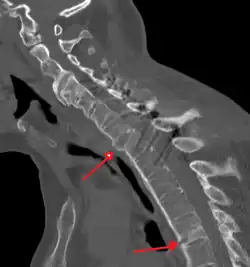

The earliest changes demonstrable by plain X-ray shows erosions and sclerosis in sacroiliac joints. Progression of the erosions leads to widening of the joint space and bony sclerosis. X-ray spine can reveal squaring of vertebrae with bony spur formation called syndesmophyte. This causes the bamboo spine appearance. A drawback of X-ray diagnosis is the signs and symptoms of AS have usually been established as long as 7–10 years prior to X-ray-evident changes occurring on a plain film X-ray, which means a delay of as long as 10 years before adequate therapies can be introduced.[25]

-

Lateral X-ray of the mid back in ankylosing spondylitis -

Lateral X-ray of the neck in ankylosing spondylitis -

X-ray showing bamboo spine in a person with ankylosing spondylitis -

CT scan showing bamboo spine in ankylosing spondylitis -

T1-weighted MRI with fat suppression after administration of gadolinium contrast showing sacroiliitis in a person with ankylosing spondylitis